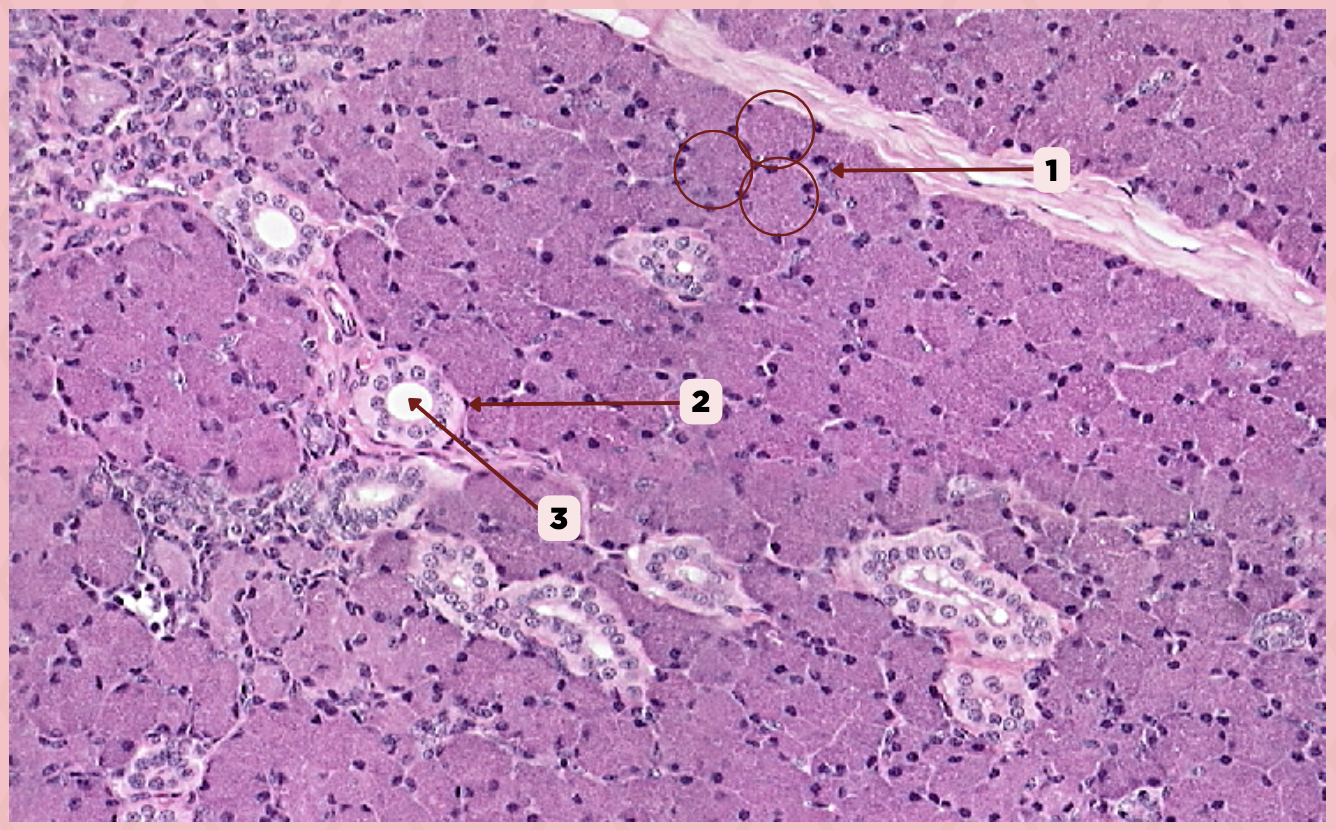

Parotid

Identify the specimen.

Capsule

Identify the structure labeled as 1.

Septa

Identify the structure labeled as 2.

Lobule

Identify the structure labeled as 3.

Lymph Node

Identify the structure labeled as 4.

Parotid

Identify the specimen.

Vein

Identify the structure labeled as 1.

Artery

Identify the structure labeled as 2.

Nerve

Identify the structure labeled as 3.

Interlobular Septa

Identify the structure labeled as 4.

Interlobular Duct

Identify the structure labeled as 5.